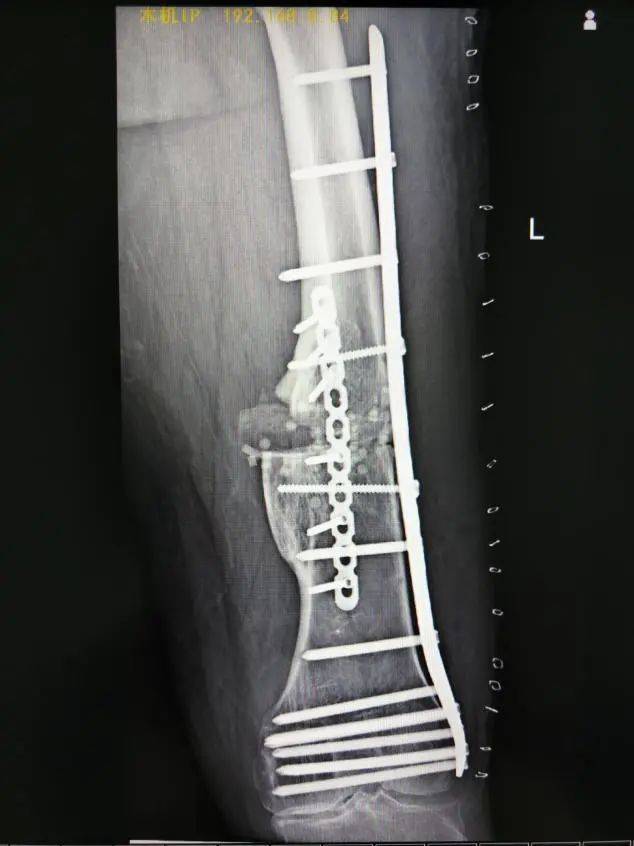

术后复查X线片影像(正位)

术中,医疗团队按照预定手术思路,首先沿左大腿中下段外侧纵形作皮肤切口,安装股骨前方截骨导板,用摆锯沿截骨导板截断股骨畸形最大处,预留股骨干外侧部分皮质。然后用撑开器沿截骨端将其撑开并放置内侧楔形导板,在C臂机透视下见经截骨矫形后现股骨干向内、向后成角畸形基本恢复,力线基本纠正。最后进行左侧股骨钢板内固定术+左侧髂骨切除术用作移植物+左侧股骨植骨术+左侧股骨人工骨植骨术。整个手术过程非常顺利。

根据患者的CT数据,重建的骨骼模型用于术前模拟,在软件端事先规划好截骨的位置以矫正肢体成角畸形、旋转与短缩,设计出截骨导板,经消毒灭菌后在手术中贴附相应骨骼部位,即可直接进行截骨。摆锯可以直接在截骨槽内截骨,并留出少量骨皮质,使得股骨在冠状位可以移动角度,然后用3D打印撑开器将截骨两端撑开。由于撑开器的两个平面是术前规划好的截骨角度面,术中可以根据截骨导板所提供的截骨角度进行完美贴合。撑开器撑开后股骨干达到对侧下肢对位对线,双下肢恢复到基本等长后,再进行接下来的股骨钢板螺钉内固定术。